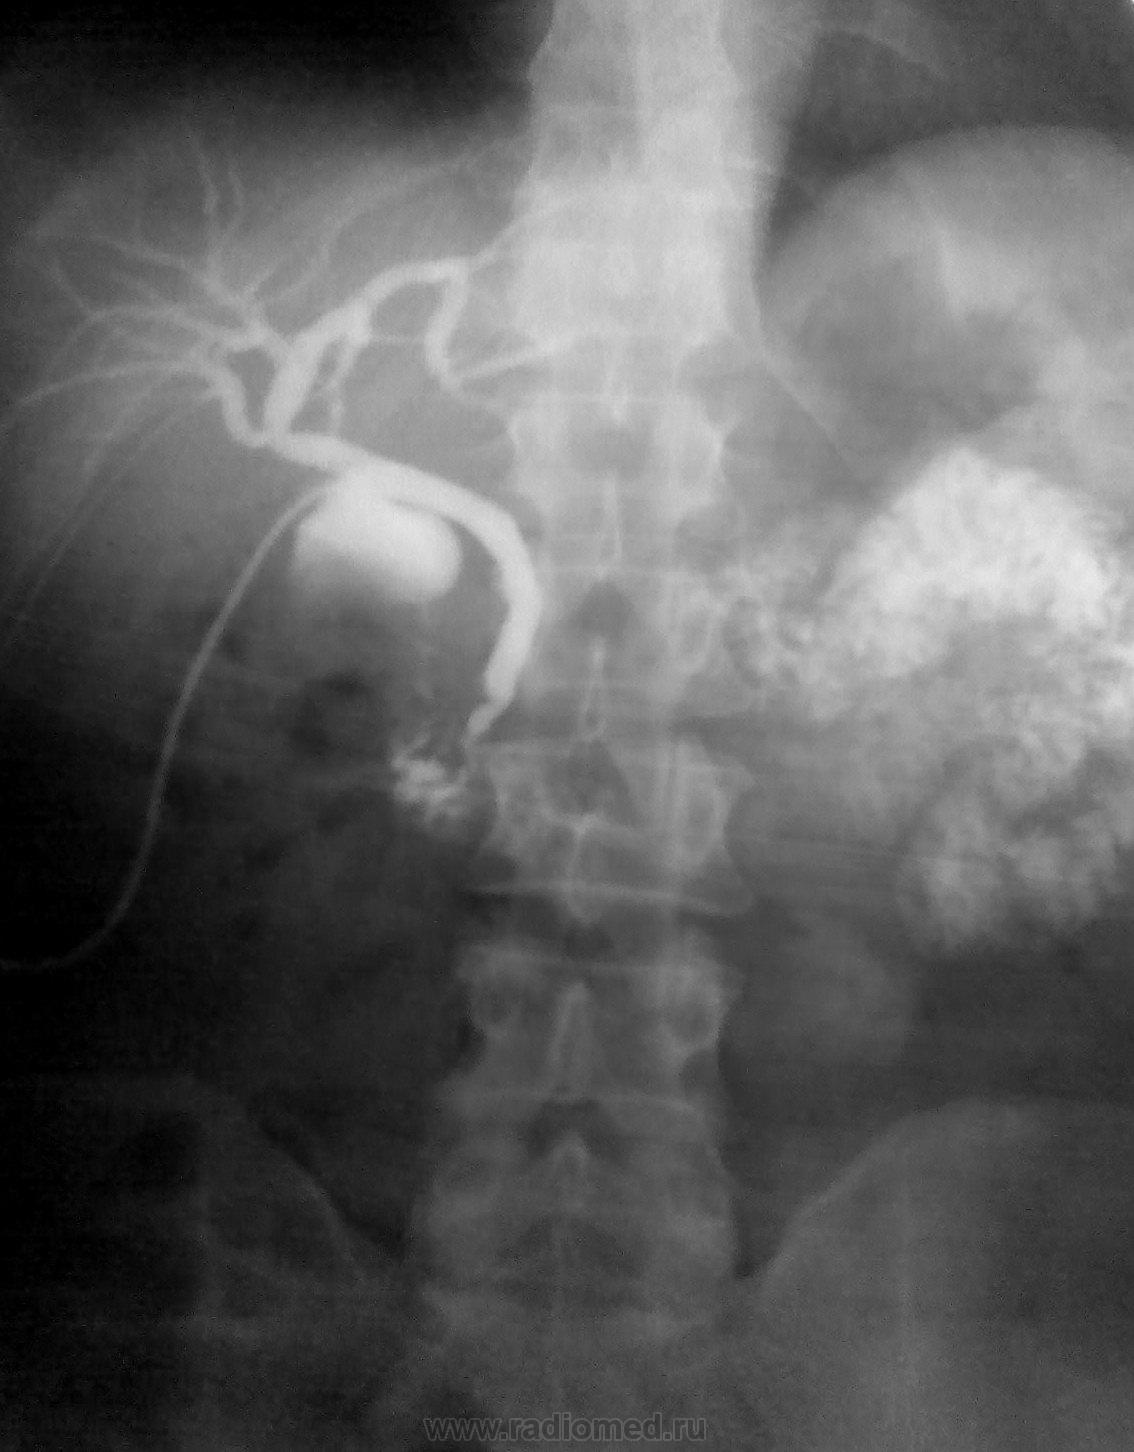

Послеоперационная чрездренажная холангиография. У хирурга был влпрос по снимку, какой, по вашему?)))

1. Хирург наоборот, луковицу 12 п кишки принял за затек...потом успокоился и заулыбался)))

На первом снимке контрастировано ложе желчного и, вероятно вследствие антиперистальтики, конраст по 12перстной вверх к желудку пошел.

Нет, коллега, это не ложе желчного, это ЛУКОВИЦА 12 п кишки, а в желудке контраста нет.

Суммация теней и всех делов...ЛДПК никуда не подводят. Снимок один - в положении лежа на спие (сейчас у меня, увы, нет цифровой скопии....), гляньте по ссылке там есть еще несколько схожих случаев. А нисходящее колено просто сократилось в этот момент...

Случай №1. Тень луковицы принял бы за затёк. Только смущало слева наличие контраста. Вероятно и дуоденальногастральный рефлюкс имеется?